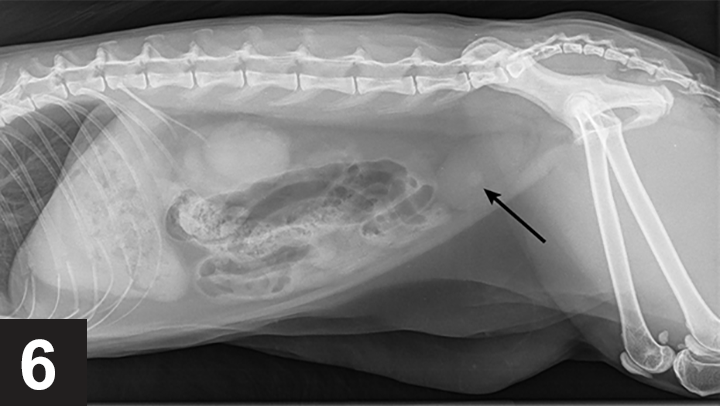

Managing Urolithiasis in Dogs Today s Veterinary Practice outlet, Bladder Stones in Dogs outlet, Managing Urolithiasis in Dogs Today s Veterinary Practice outlet, Bladder Stones in Dogs outlet, Why you see them why you don t Radiographs and uroliths outlet, Find Those Urinary Bladder Stones New Vet Equipment outlet, Bladder Stones in Dogs outlet, Urolith Center outlet, Lateral abdominal radiograph of a male entire Rottweiler dog. The outlet, Struvite Stones Canine Mar Vista Animal Medical Center outlet, Bladder Stones in Dogs outlet, Urolithiasis in Small Animals Urinary System Merck Veterinary outlet, Imaging of Calculi of the Urinary System outlet, Bladder Stones in Dogs outlet, Bladder Stones in Canines outlet, Ammonium Urate Urolithiasis outlet, Bladder Stones in Dogs Diagnosis and Treatment PetCoach outlet, Bladder Stones in Dogs outlet, Imaging of Calculi of the Urinary System outlet, Cystotomy to Remove Urolith Wellness Veterinary Hospital outlet, A less usual case of canine urolithiasis Companion Animal outlet, Evaluation of a dry therapeutic urinary diet and concurrent outlet, Urinary Stones outlet, Find Those Urinary Bladder Stones New Vet Equipment outlet, Why you see them why you don t Radiographs and uroliths outlet, Evaluation of a dry therapeutic urinary diet and concurrent outlet, Treatment and Prevention of Kidney and Bladder Stones Whole Dog outlet, Imaging of Calculi of the Urinary System outlet, Urolithiasis in Small Animals Urinary System Merck Veterinary outlet, Diet for Dogs with Urate Stones Elmo s Kitchen outlet, Bladder Stones in Dogs Complete Guide Emergency Vet 24 7 outlet, Cystotomy to Remove Urolith Wellness Veterinary Hospital outlet, Different Types of Bladder Stones in Dogs Dog Discoveries outlet, Ventro dorsal abdominal X ray showing bilateral kidney enlargement outlet, DogAware Articles Urate Cystine and Less Common Urinary Stones outlet.